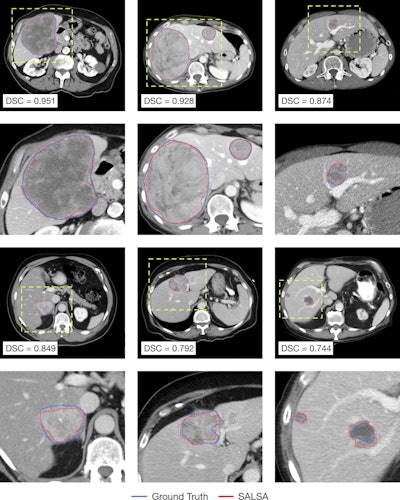

In parallel, the tumor masks automatically generated by SALSA exhibit good overlap with the ground truth. Both approaches reported high values in segmentation metrics for the test and external validation cohorts.

Visual inspection of the automatically delineated contours. Representative cases of liver tumors delineated by SALSA (red) alongside the ground truth (blue) segmented masks. Yellow-dashed boxes indicate the magnification done for better visualization. Image courtesy of Maria Balaguer-Montero, Dr. Raquel Perez-Lopez et al and presented at ECR 2025.